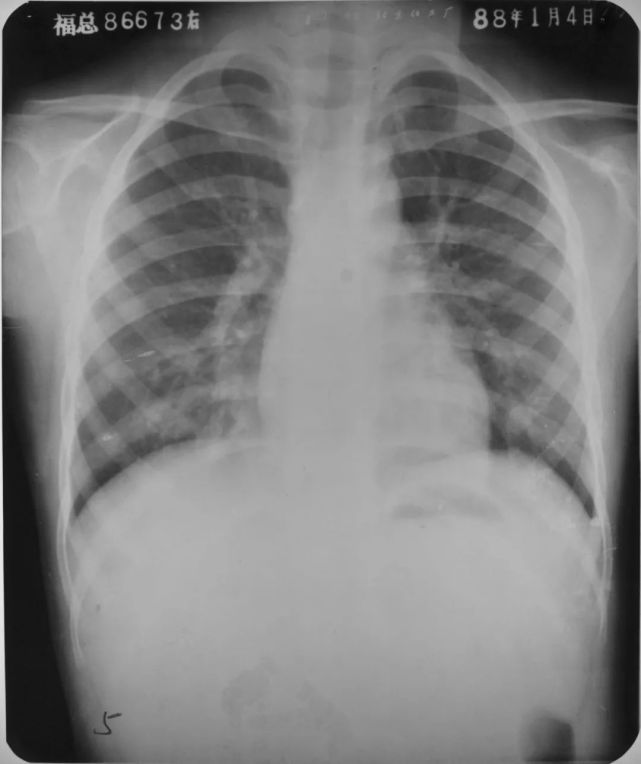

双肺化脓性肺炎

图片

胸部正位片示:两肺多发小片状密度增高影,边缘模糊。另见大小不等的圆形或椭圆形结节状阴影,边缘较清楚,部分可见空洞